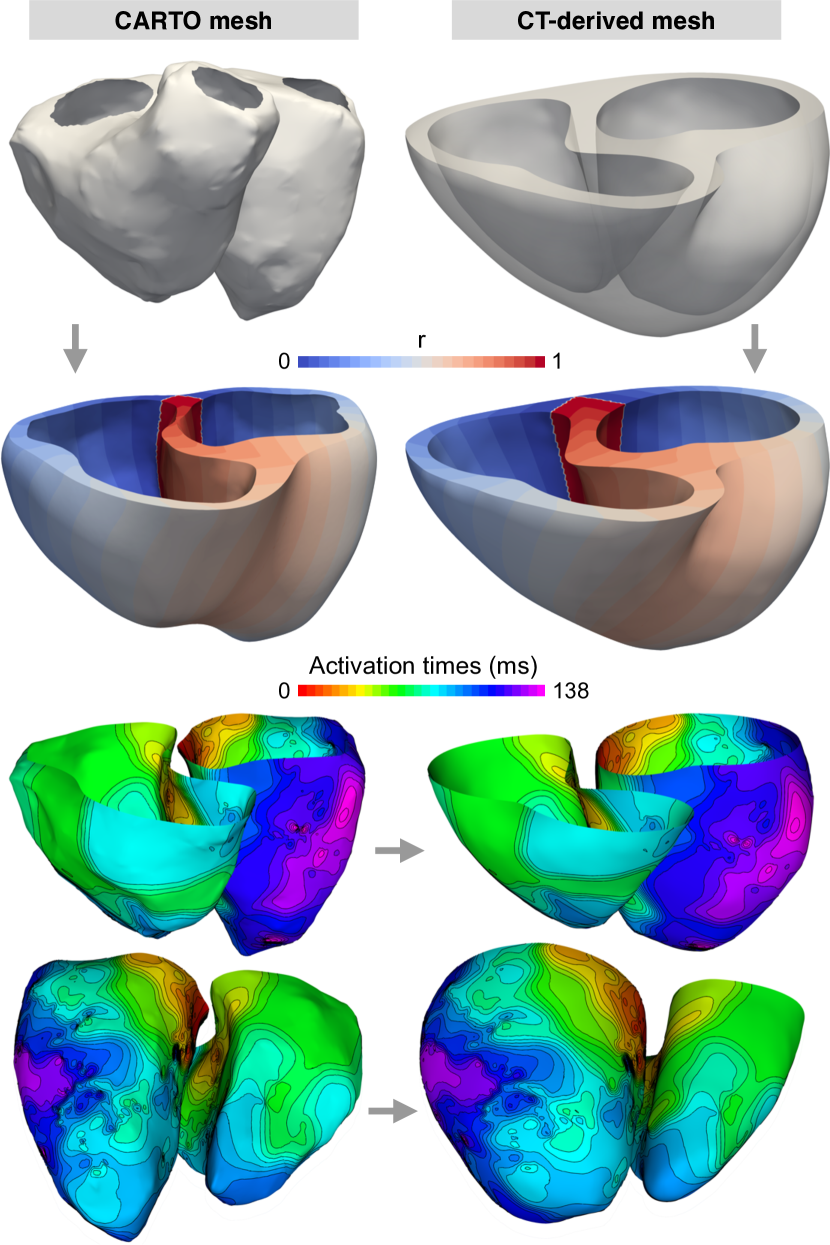

5.2 Transfer of activation times

Another application is the integration of data from electroanatomical mapping and tomographic imaging. Fig. 20 shows an example for the transfer of activation times recorded using the CARTO mapping system (Biosense Webster, Inc., Irvine, USA) onto the corresponding surfaces of a volume mesh created from CT images. To compute Cobiveco, the endocardial surfaces from CARTO were first converted into a volume mesh (see Fig. S6 for a rule-based pipeline to create a volume mesh from only endocardial surfaces). The coordinates obtained on both geometries were then utilized to transfer the activation times.

In contrast to nearest-neighbor mapping [10, 13] or other straightforward methods [3], Cobiveco allows a continuous and bijective mapping between geometries from both modalities. We believe that an unwanted smoothing of activation times should not motivate a discontinuous mapping between both geometries [10] but should be addressed by an appropriate spatial upsampling on the source geometry.